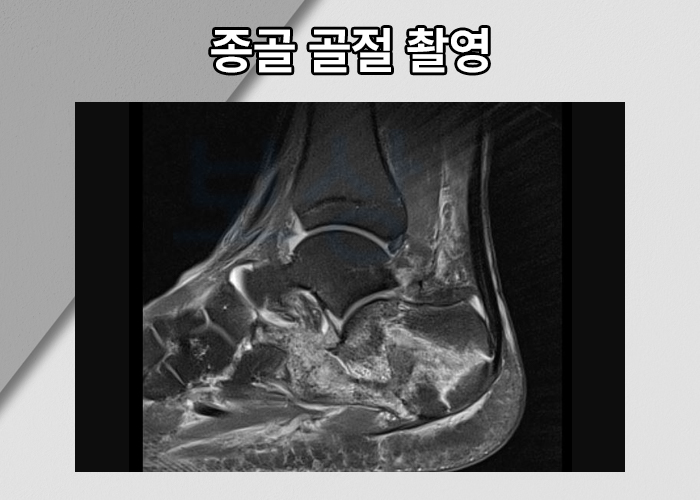

발뒤꿈치 골절은 흔히 높은 곳에서 떨어지는 추락사고로 인해 발생합니다. 충격이 크기 때문에 대다수 분쇄골절의 형태를 띄는데요, 지면에 많이 닿고 사용되기 때문에 회복이 쉽지 않고, 관절염이 잔존할 가능성이 높은 진단입니다. 발뒤꿈치 골절 수술 받은 후 발목의 움직임이 예전같지 않은 분들이 많습니다. 특히 좌우로 움직이는게 쉽지 않아 힘들어하시죠.

문제는 여전히 발목의 움직임이 쉽지 않았습니다. 재활치료를 해도 나아지는 것 같지 않았고 받을 수 있는** 보상이 있다면 최대한 받고 싶어 하셨습니다.** 저희는 의뢰인의 **영상CD, 의무기록, 진단서 **등을 받아 면밀한 분석을 도와드렸습니다. 의뢰인의 종골 골절은 발목 관절면과 닿아있는 부위인 것에 더해 족관절의 발목 인대까지 파열된 상황이었죠.